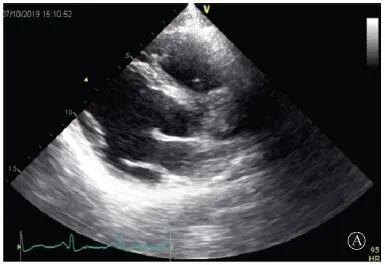

A:胸骨旁长轴平面,左室舒张末内径略增大,室壁无明显增厚;

图3 患者入院后超声心动图